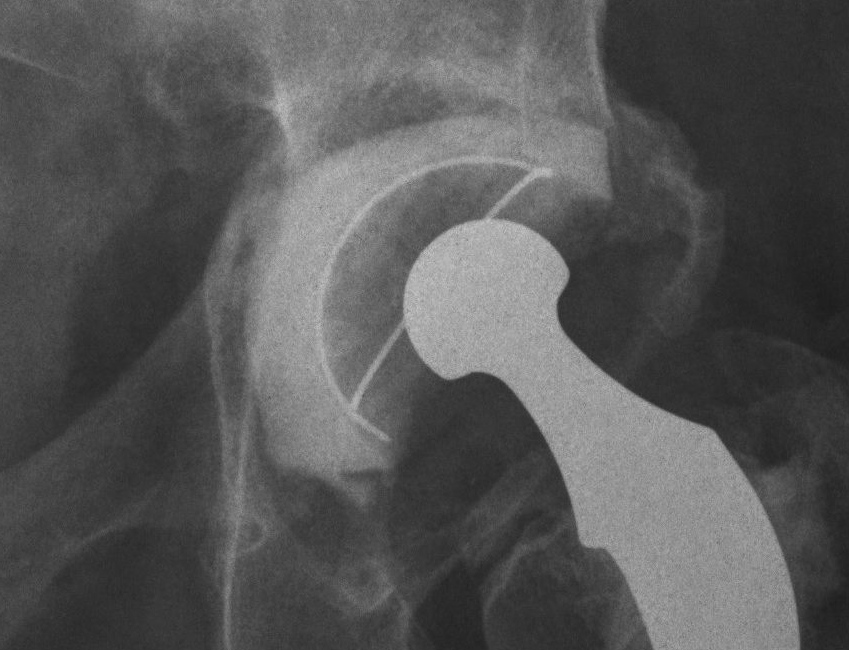

Paprosky Classification

Based on ability of the remaining host bone

- to provide initial stability to a hemispherical cementless acetabular component

- until ingrowth occurs

Type 1

Undistorted rim

- anterior and posterior columns intact

- no superior migration

- may have some contained deformities

- ishium, teardrop and Kohlers line intact

Type 2

Distorted but intact rim

- can support a hemispherical cementless implant

Some distortion, minimal superior migration

- at least 50% good support by host bone

- anterior and posterior columns intact

- no substantial osteolysis of ischium or teardrop

2A

- superomedial migration but superior rim intact

2B

- < 1/3 superior deficit

- remainder is still supportive

- replace with allograft for bone stock

2C

- medial migration to Kohlers, but wall intact

- rim is supportive

- manage as for protrusio

Type 3

Non supportive rim

- columns not supportive, superior migration> 3 cm

- require structural allograft for support

4 radiographic criteria

1. Superior migration of the hip centre

- indicates damage to anterior and posterior columns

- supero-medial indicates greater damage to anterior column

- supero-lateral indicates greater damage to posterior column

2. Ischial osteolysis

- bone loss inferior posterior column

3. Teardrop osteolysis

- inferior anterior column and medial wall

4. Position of the implant relative to Kohler’s line

- deficiency of anterior column

3A

- > 40% host bone contact

- < 50% rim missing

3B

- < 40% host bone contact

- > 50% rim missing